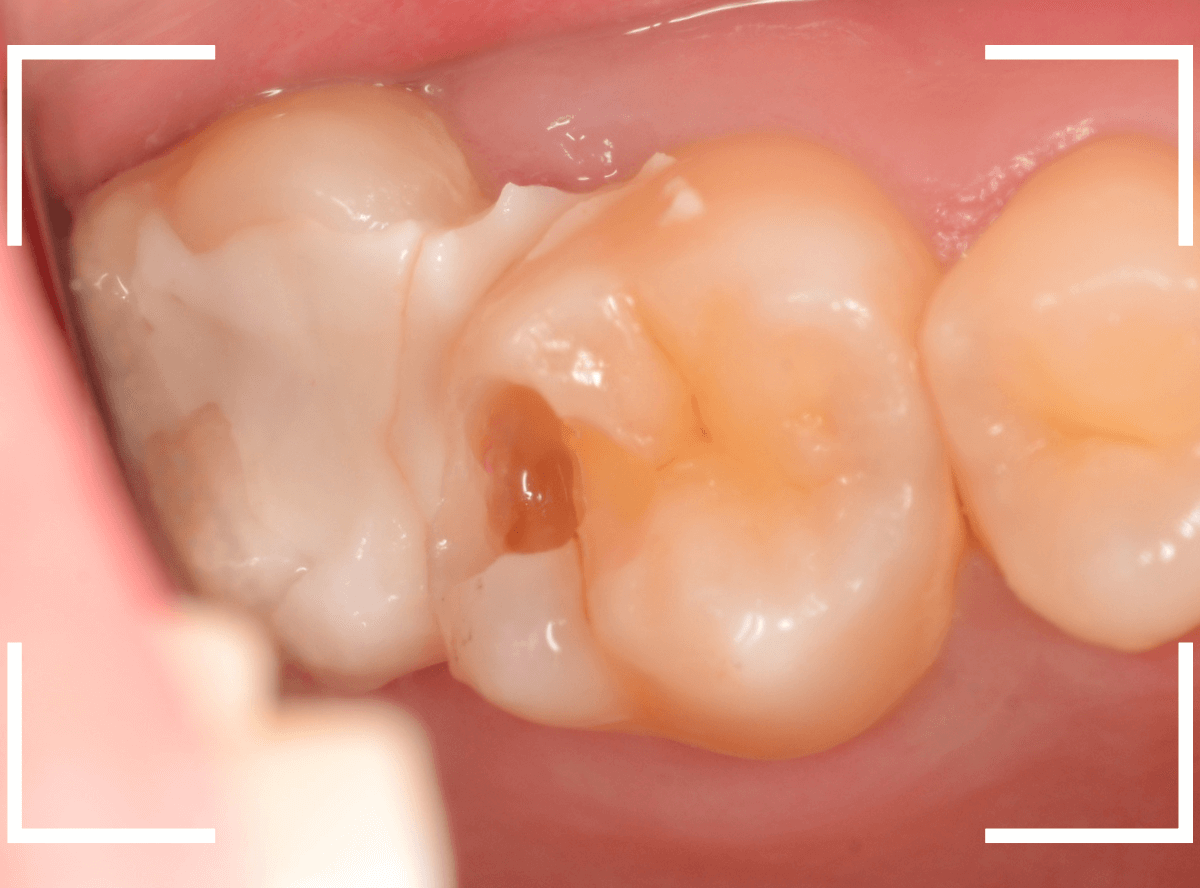

Case.24 レジンの下で虫歯が進行

上の奥歯の虫歯が見つかった患者さんです。

初診のチェックの際に、上から目視すると、レジンがつめてある〇部分が薄暗く黒くなっているので、これは虫歯があるな、とわかりました。

レントゲン写真で確認します。

先ほどの黒く見えた部分は少し削るとすぐに虫歯が出てきました。

手前の歯まで虫歯を除去した時点で、う蝕検知液で確認します。

赤く染色されている部分が虫歯です。

思ったよりも深めの虫歯ですね。

レジンを除去して虫歯をすべて治療したところです。

レジンの中も全体にうっすらと虫歯になっていました。

このくらいの虫歯でも、患者さんは自覚症状はありませんでした。